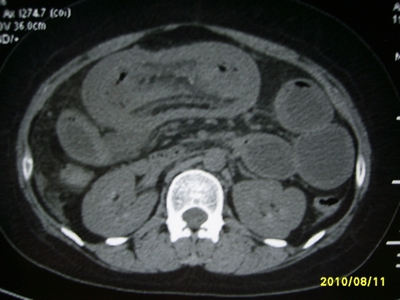

5天前突发腹痛剧烈难忍,伴解淡血水样便。近一天来腹痛缓解,没有明显的腹膜炎的体征。今天照的腹部ct。从ct上看感觉是一个绞窄性肠梗阻,但是现在没有腹痛。不好解释

要有麻烦了,感觉小肠有套叠还有扭转改变,估计部分已有坏死。

高位肠梗阻(不全性),原因小肠(空肠)扭转,肠壁水肿增厚,成年人肠梗阻要排除合并占位,建议手术。

绞窄性肠梗阻_肠管套叠 扭转,肠壁明显水肿。

病人现在没有腹痛。怪了。从影像上来看。确实是绞窄了。但是没有腹痛。没有明显的腹膜炎的体征。确实有不好解释。难道是坏死了。反而不痛了。怪怪怪

支持绞窄性肠梗阻,肠壁明显水肿并见有多发小泡状积气--肠坏死

考虑绞窄性肠梗阻并肠坏死。